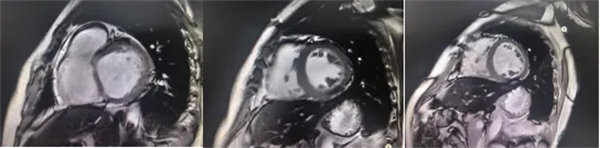

在常规心脏MRI检查中,医学影像科发现患者心肌异常表现,考虑铁过载性心肌病,为明确诊断要进一步加做铁定量技术,加扫T2 mapping序列。CMR铁定量技术是目前评估心肌铁含量的“金标准”,能够快速、无创、精准量化心肌内铁沉积程度,检查结果提示患者局部心肌T2*值显著低于正常范围,符合铁过载性心肌病的诊断标准。

基底部、中间部及心尖部 局部心肌T2*值明显减低T2* 10-20/s, 部分小于10/s

心肌信号局部减低 呈现“黑色心肌”表现,这是由于铁沉积导致局部磁场不均匀,引起信号丢失(失相位)。